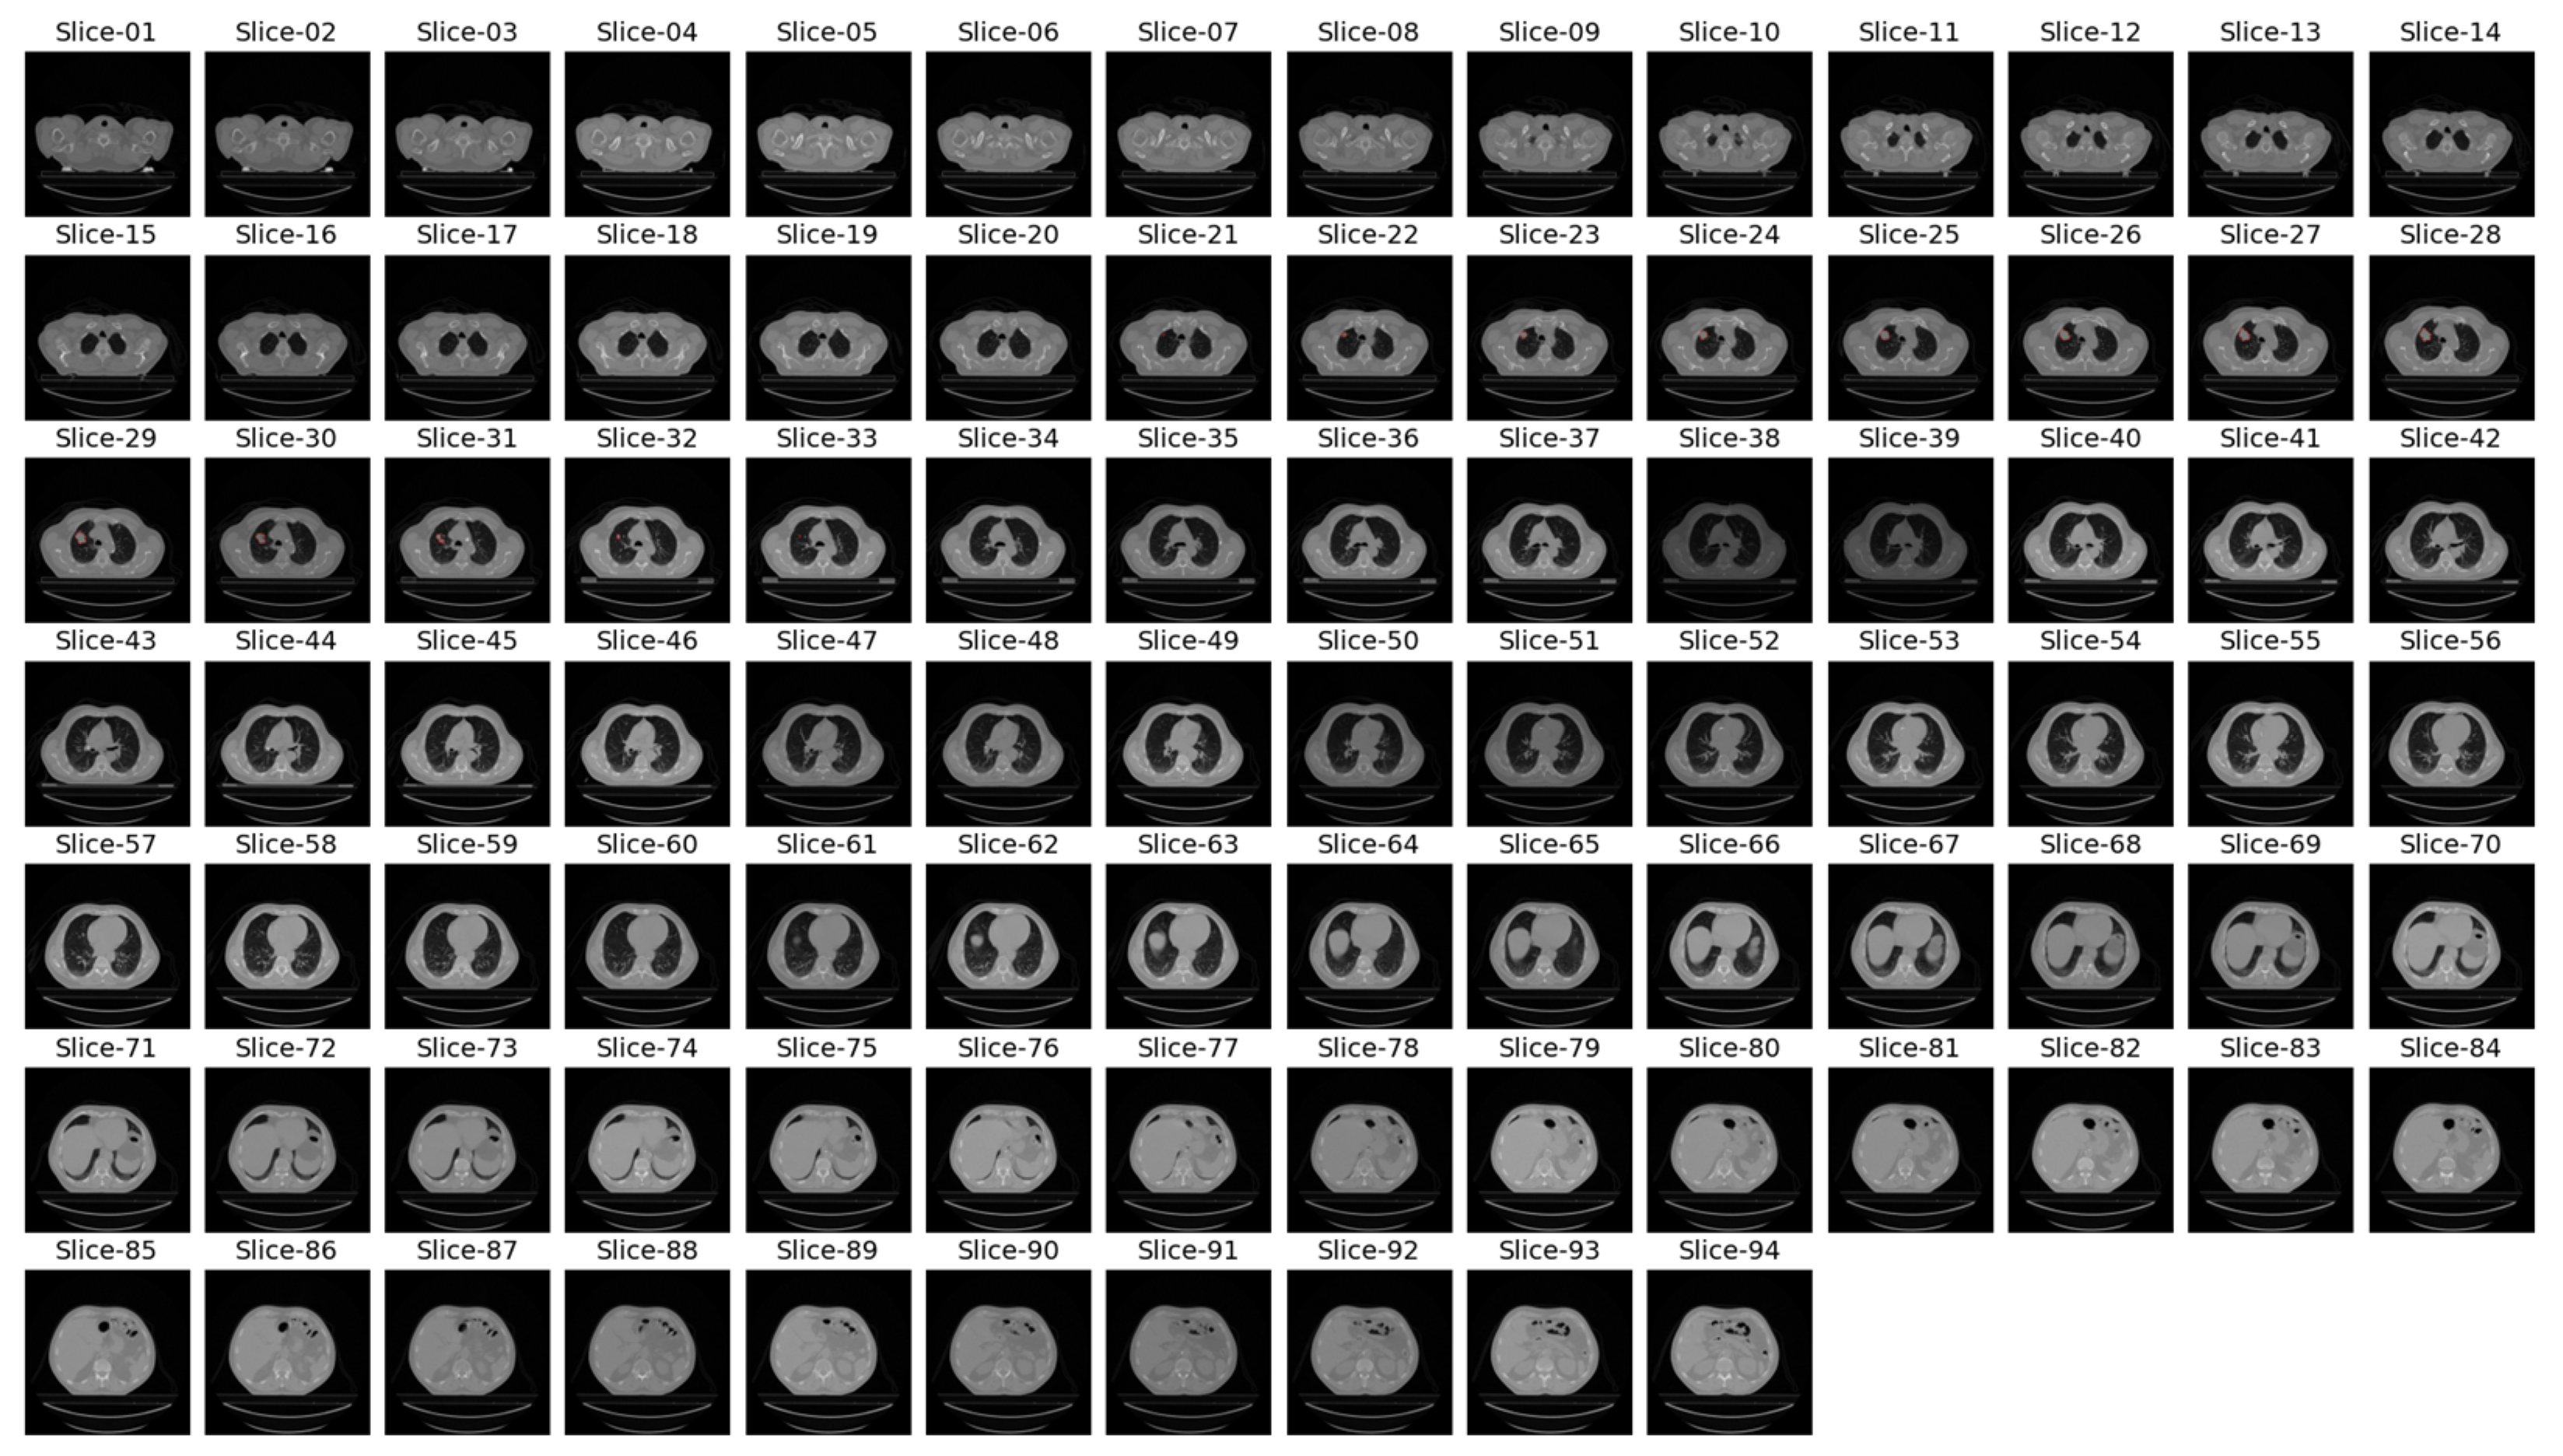

In the previous literature addressing similar problems to ours, only tumor regions from patients labeled as GTV-1 were utilized. The dataset contains a variable number of images with GTV-1 labeled tumors, ranging from 2 to 97. Figure 4 shows CT slices from a patient (LUNG1-243) with GTV-1 regions marked. There are 94 slices and 13 GTV-1 labeled tumor regions (Slice 21 through Slice 33) for this patient. For all patients in the dataset, Slice Thickness is given as 3.0 mm and Pixel Spacing is 0.977 mm.